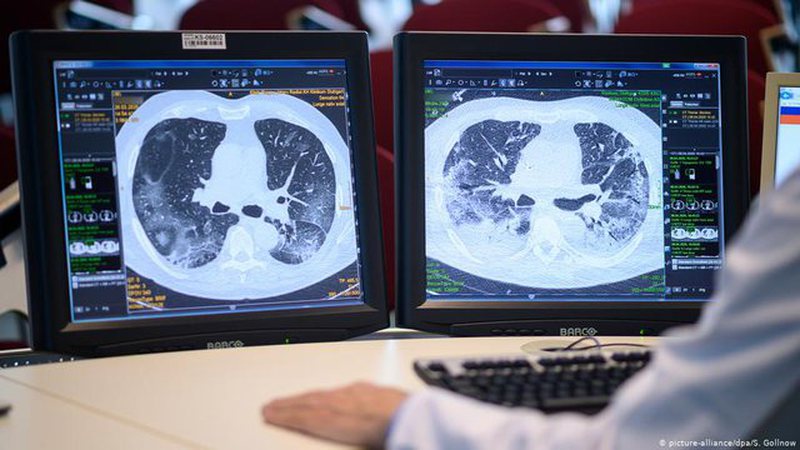

Koronavirusi mund të lërë pasoja edhe të njerëzit që e kanë kaluarpka simptoma. 70% e personave të prekur nga koronavirusi, por që janë asimptomatikë, mund të ndjejnë pasoja në disa organe të tyre 4 muaj pas infektimit.

“OBSH po vëren efekte dytësore në zemër, mushkëri, shëndet mendor dhe tru”.